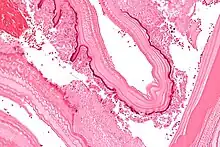

From the embryo released from an egg develops a hydatid cyst, which grows to about 5–10 cm within the first year and is able to survive within organs for years.[25] Cysts sometimes grow to be so large that by the end of several years or even decades, they can contain several liters of fluid. Once a cyst has reached a diameter of 1 cm, its wall differentiates into a thick outer, non-cellular membrane, which covers the thin germinal epithelium. From this epithelium, cells begin to grow within the cyst. These cells then become vacuolated, and are known as brood capsules, which are the parts of the parasite from which protoscolices bud. Often, daughter cysts also form within cysts.[24]

The cysts found in those with cystic echinococcosis are usually filled with a clear fluid called hydatid fluid, are spherical, and typically consist of one compartment and are usually only found in one area of the body. While the cysts found in those with alveolar and polycystic echinococcosis are similar to those found in those with cystic echinococcosis, the alveolar and polycystic echinococcosis cysts usually have multiple compartments and have infiltrative as opposed to expansive growth.[11][12]

A formal diagnosis of any type of echinococcosis requires a combination of tools that involve imaging techniques, histopathology, or nucleic acid detection and serology. For cystic echinococcosis diagnosis, imaging is the main method—while serology tests (such as indirect hemagglutination, ELISA (enzyme linked immunosorbent assay), immunoblots or latex agglutination) that use antigens specific for E. granulosus verify the imaging results. The imaging technique of choice for cystic echinococcosis is ultrasonography, since it is not only able to visualize the cysts in the body's organs,[30] but it is also inexpensive, non-invasive and gives instant results.[31] In addition to ultrasonography, both MRI and CT scans can and are often used although an MRI is often preferred to CT scans when diagnosing cystic echinococcosis since it gives better visualization of liquid areas within the tissue.[30][32]